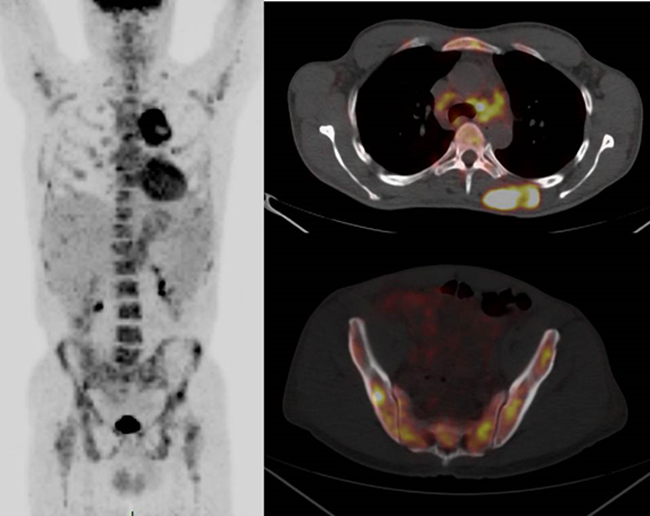

A recent study from CEREMAST reported on the patterns of FDG-PET/CT in systemic mastocytosis [7]. FDG uptake does not appear to be a sensitive marker of MC activation and proliferation because no significant FDG uptake was observed in most common forms of mastocytosis, notably aggressive SM. However, in this study, all 3 patients with a MCS exhibited a pattern mimicking solid tumor metastasis. The standardized uptake value (SUV) was observed to be intense (range: 3.8-12.2). The sites of disease activity were the bone marrow and axial and proximal appendicular skeleton (Figure 4). These observations suggest a role for FDG-PET as a useful tool for diagnostic and therapeutic assessment in MCS.

Figure 4: FDG-PET/CT in mast cell sarcoma. The sites with confirmed disease are the bone marrow and axial and proximal appendicular skeleton (Figure 4). MIP (maximum intensity projection) image and axial fusion images. Soft tissue mass (dotted arrow) and mediastinal adenopathies (arrowhead) are shown here with multifocal bone marrow uptake.